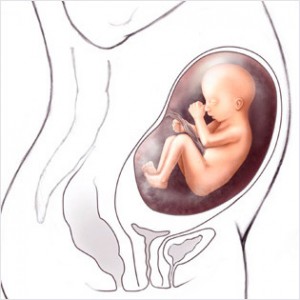

Bu haftadan itibaren artık bebek rahim içerisinde oldukça fazla yer kaplar ve bu yüzden ona hareket edecek fazla alan kalmaz. Eğer bebeğinizin hareketlerinde azalma his ederseniz endişe etmeyin, hareketlerin azalması bu yüzdendir.

Bebeğin Boyutu: 43.7 cm, 1.9 kg

Hamileliğin (Gebeliğin) 35. Haftası Resim ve Video;